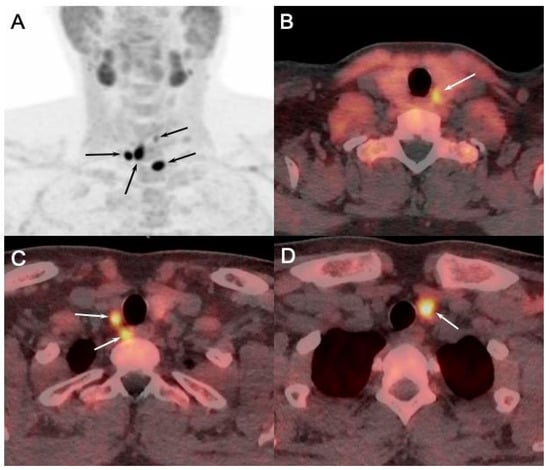

Figure 6. [18F]FCH PET/CT ((A): anterior MIP; (BD): axial fusion images) performed in 23-y-old MEN1 patient with asymptomatic primary hyperparathyroidism (PTH: 389 ng/L; calcemia: 2.71 mmol/L) showing pathologic [18F]FCH uptake in both superior and inferior parathyroids (arrows). Pathology after surgical excision confirmed presence of parathyroid adenomas.

PET/CT utilizing 18F-labeled choline analogs demonstrates excellent results, with detection rates exceeding 90%, and reported sensitivity of 95% and PPV of 97% on a per-patient analysis, and 92% and 92% in a per-lesion analysis, respectively [36]. A recent meta-analysis reported the superiority of [18F]FCH PET/CT compared to conventional imaging methods, with a sensitivity of 92% for [18F]FCH PET/CT and 65% for a combination of conventional methods in the setting of sporadic sHPT (Figure 6) [12].